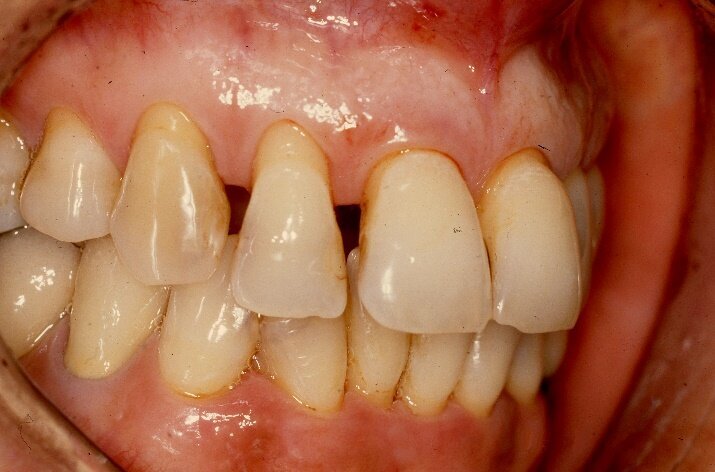

La paziente (che agirà in giudizio) 55 anni, fumatrice con scarso controllo dell’igiene domiciliare, in cura nel 1998 per parodontopatia cronica e compromissione dei quattro incisivi superiori (Figg. 1-5) per dodici anni, viene trattata con terapie chirurgiche e non2. Nel luglio 2010, dopo ben 12 anni di mantenimento di tali denti, si presenta all’osservazione dell’odontoiatra per la rottura dello splintaggio, riferendo di aver subito un accidentale trauma facciale.

Il dentista verifica un aggravamento della mobilità dei quattro incisivi e sollecitato dalla paziente a migliorare l’aspetto estetico, prospetta la sostituzione degli elementi naturali da estrarre, con una protesi fissa su impianti. Al fine di ridurre il rischio di un ulteriore riassorbimento dell’osso alveolare residuo e del collasso dei tessuti molli3-7 della pre-maxilla, prima delle estrazioni degli incisivi, viene prospettata la loro estrusione8, 9.